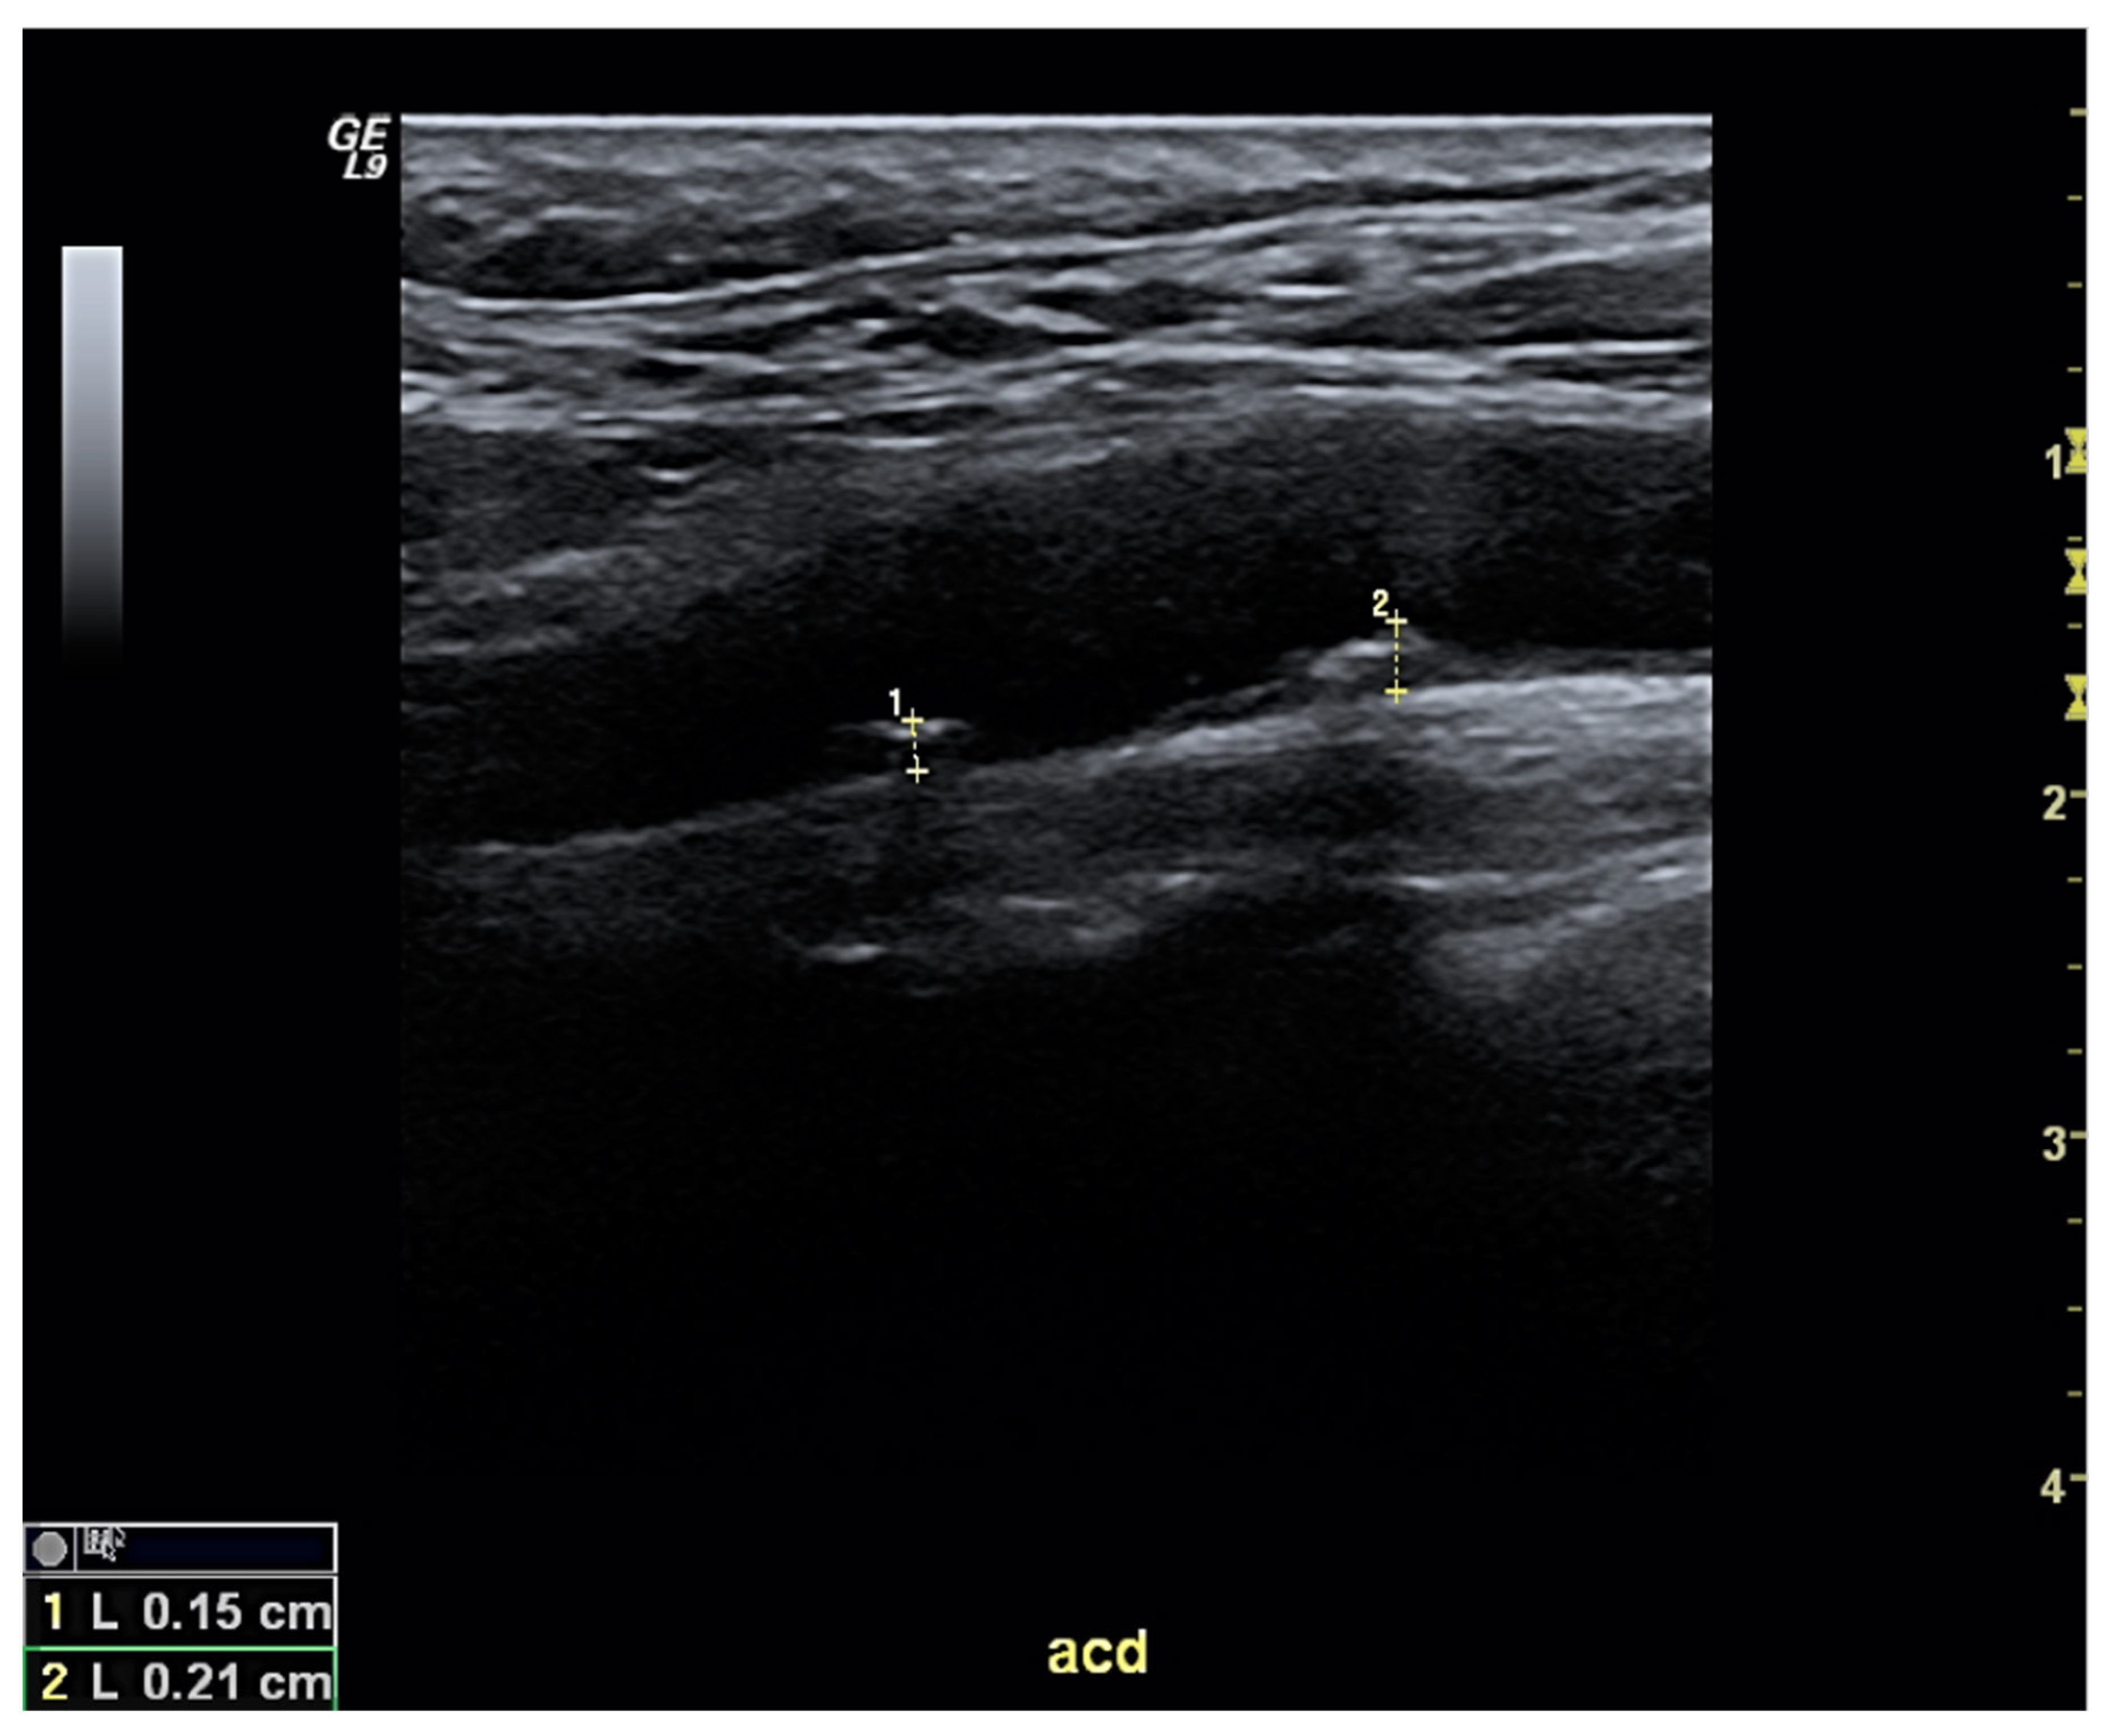

The screening for subclinical atherosclerosis using ultrasound is simple, accessible, and reliable—especially for carotid arteries (Figure 1), which carry prognostic consequences. The European cardiovascular guidelines recommend that the identification of subclinical atherosclerosis should prompt the physician to classify the patient as being in the highest cardiovascular risk category [85], since this factor independently predicts both coronary and cerebrovascular events [86,87]. On the other hand, the guidelines caution against making risk estimations based on intima-media thickness measurements. The reported prevalence of carotid atheroma plaques in patients with gout ranges from 29.1% to 59.2% [13,49,88,89,90,91]—percentages that vary depending on several factors (such as patient demographics and/or disease duration). In any case, the percentage is likely higher than in people without gout. Our group demonstrated that a cardiovascular screening strategy incorporating risk assessment tools and carotid ultrasound is capable of reclassifying the risk of more than half of new gout patients seen in rheumatology clinics, with two-thirds of them ultimately meeting the very-high risk level threshold [13].

Figure 1.

Ultrasound of right carotid artery, longitudinal view, in a patient with gout who had a moderate cardiovascular risk as assessed by scores. The exam revealed two atheroma plaques, mildly calcified, of 1.5 mm (1) and 2.1 mm (2) thickness. According to current European guidelines, this patient should be classified as having a very high cardiovascular risk and managed accordingly.